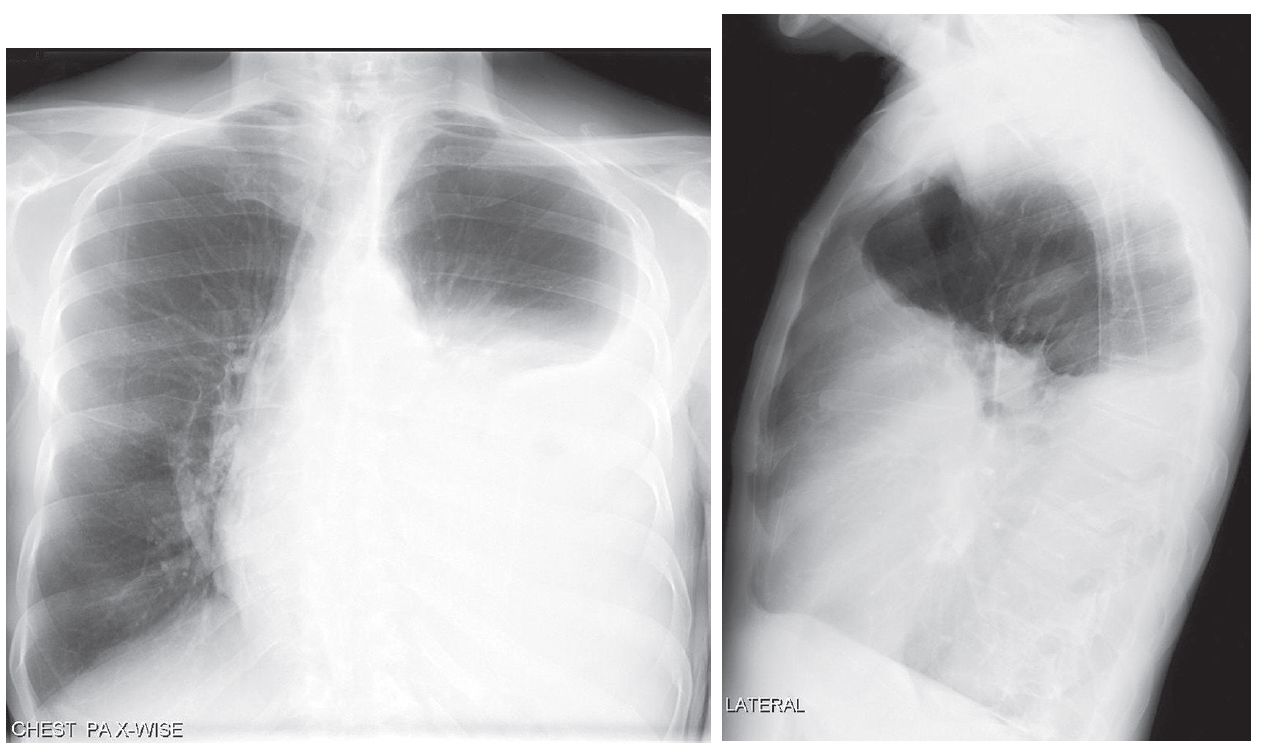

72-year-old Man with Dyspnea and Left-sided Pleuritic Chest Pain

72-year-old man with long-standing history of chronic obstructive lung disease presents to his physician with progressive dyspnea over the last several weeks and left-sided pleuritic chest pain.

What is the Diagnosis ?